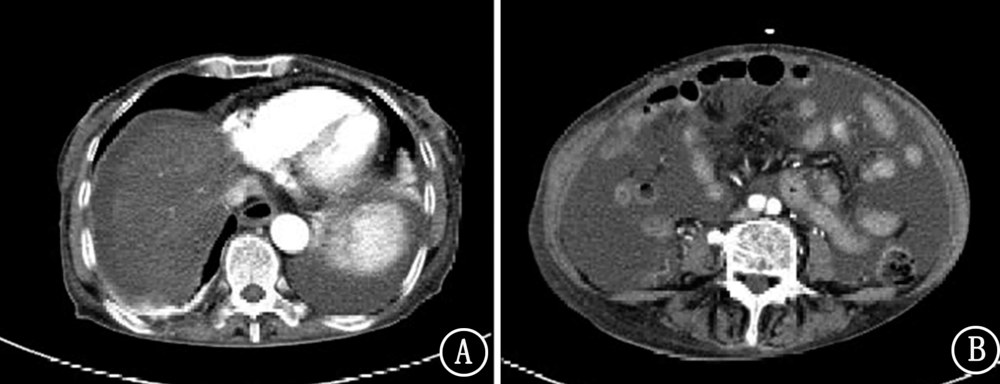

晚期胃癌目前无明确有效治疗手段,现报道1例安罗替尼治疗晚期胃癌病例,并对其临床疗效和安全性进行分析。